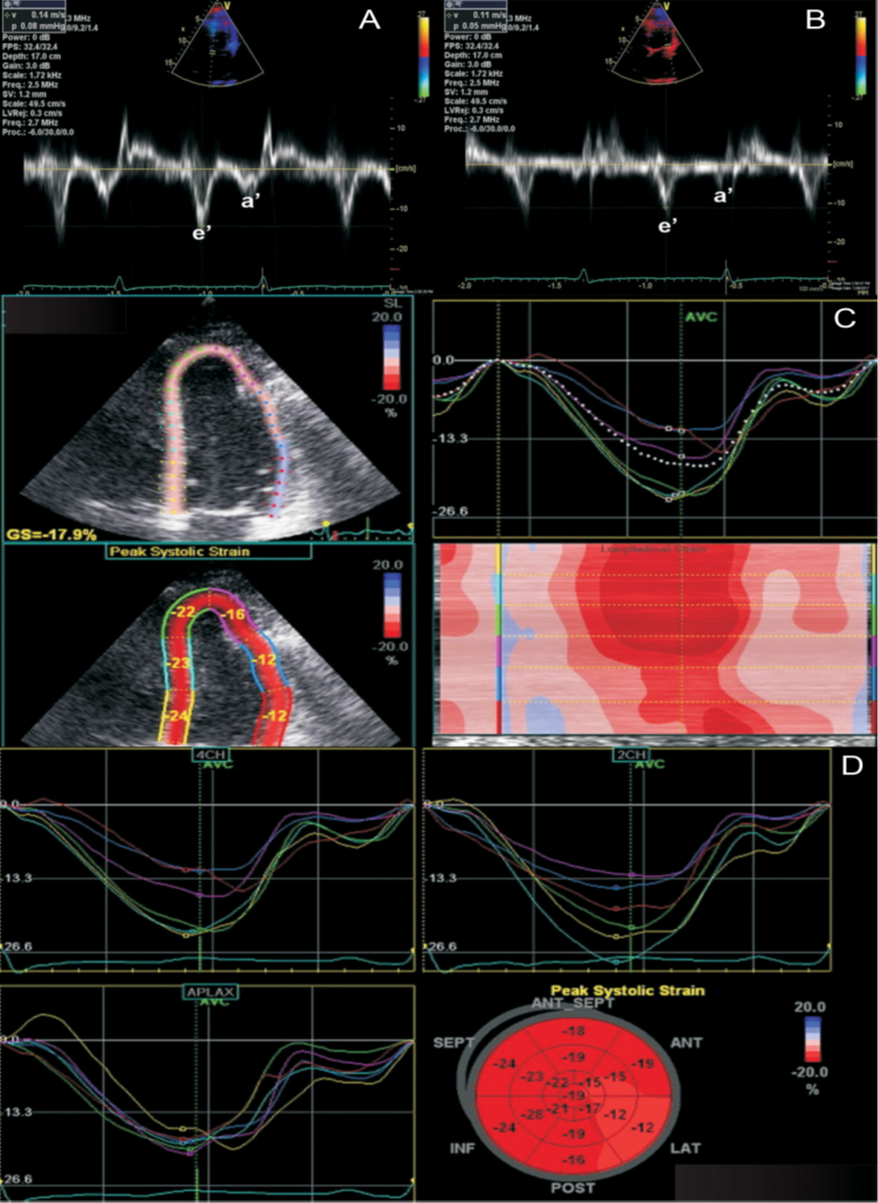

В диагностике констриктивного перикардита также может быть полезна тканевая допплерография, демонстрирующая так называемый феномен “annulus reversus”, заключающийся в том, что нормальная или повышенная ранняя диастолическая скорость движения медиальной части митрального кольца (медиальная е') оказывается выше, чем ранняя диастолическая скорость движения латеральной части фиброзного кольца (латеральная е’) (Приложение А3, рис. А3-2) [117].

Сочетание разнонаправленного смещения МЖП в зависимости от фаз дыхания с увеличением ранней диастолической скорости движения медиальной части митрального кольца (медиальная е') ≥9 см/сек имеет самую высокую диагностическую чувствительность (87%) и специфичность (91%) [118].

При эхокардиографическом исследовании для выявления констрикции перикарда могут быть использованы дополнительные показатели, в том числе деформация (strain). При констриктивном перикардите глобальная продольная деформация обычно сохранена, тогда как окружностная (циркулярная) деформация, скручивание и раннее диастолическое раскручивание снижены [119]. Этот тип нарушения деформации, “strain reversus”, является аналогом “annulus reversus”, выявляемым при проведении тканевой допплерографии. Показано, что это нарушение является обратимым после проведения перикардэктомии [119].

Допплер-ЭхоКГ позволяет определить парадокс кольца. Он заключается в том, что при относительном сохранении способности миокарда растягиваться в продольном направлении деформация продольной оси левого желудочка и продольная ранняя диастолическая скорость либо нормальные, либо, по мере прогрессирования констриктивного перикардита, увеличиваются. В то время как при рестриктивной кардиомиопатии или при заболеваниях миокарда происходит снижение этих показателей. При этом усредненная максимальная тканевая скорость раннего диастолического смещения септальной части митрального кольца выше латеральной (Приложение А3, рис. А3-5) [117, 123, 124–128]. Несмотря на высокую чувствительность и специфичность (95% и 96% соответственно), ограничение данного признака при диагностике будет проявляться в случае неоднородности поражения перикарда или при кальцификации кольца митрального клапана.

Характерно динамическое изменение атриовентрикулярного кровотока в зависимости от фазы дыхания (Приложение А3, рис. А3-6), что отличает констриктивный перикардит от рестриктивной кардиомиопатии. На вдохе пиковая скорость крови уменьшается, а время изометрического расслабления желудочков увеличивается. На выдохе — атриовентрикулярный кровоток возвращается к нормальным значениям. Как правило, прирост пиковой скорости составляет ≥25% на вдохе по сравнению с выдохом [129]. Этот признак обладает 85% чувствительности и 90% специфичности [118].